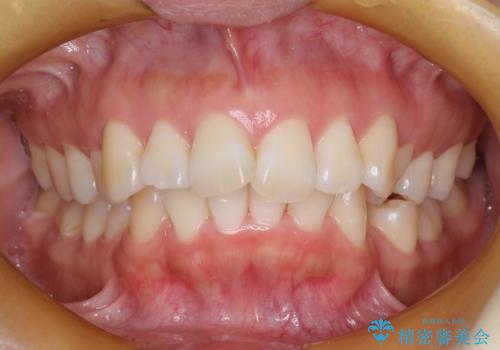

抜歯をして前歯を下げ、ガタつきを取り除く ワイヤー矯正

- 上顎両側第1小臼歯、下顎左側第2小臼歯の3本を抜歯、ラビアルのワイヤー矯正を計画した。